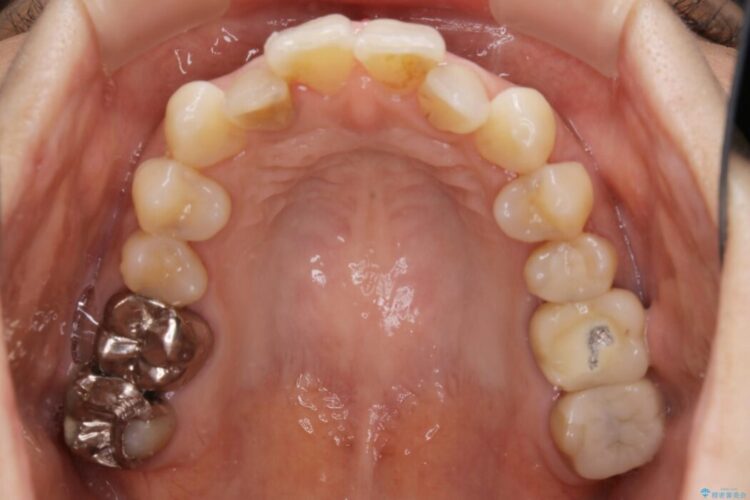

全体的に歯列が狭窄しており、本来外側に覆いかぶさっている上の前歯が内側に入り込んでいました。

歯列弓全体の形状を整えるとともに歯の大きさもコントロールすることで非抜歯にて矯正を行いました。